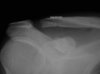

"Resection" in this case typically involves REMOVAL of a small portion of the clavicle (AKA Mumford procedure) as shown in the top Xray. Many SM docs will also "shave" the undersurface of the acromium if doubt exists.

Both procedures are done arthroscopically and have a short, several week,, recovery period.

Nonetheless an MRI might be helpful to establish the problem is localized to the

A-C joint